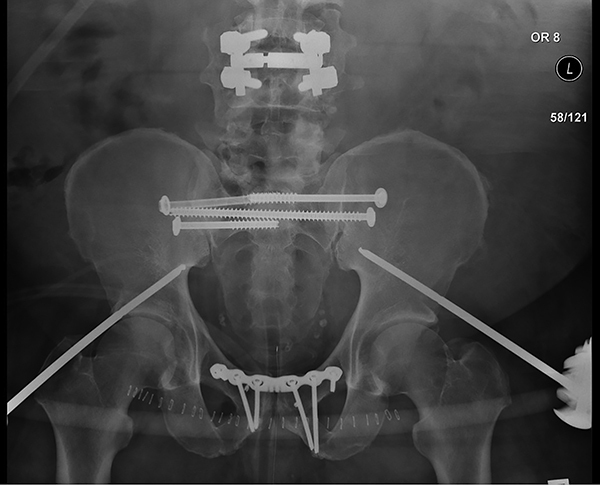

Figure 3. Internal Fixation of Pelvic Fracture |

Patient originally stabilized with external fixation was bridged to definitive stabilization of the anterior and posterior elements with internal fixation. Source: Uzcategui M, Menaker J. Blunt pelvic trauma. Trauma Reports 2014;15:7. |